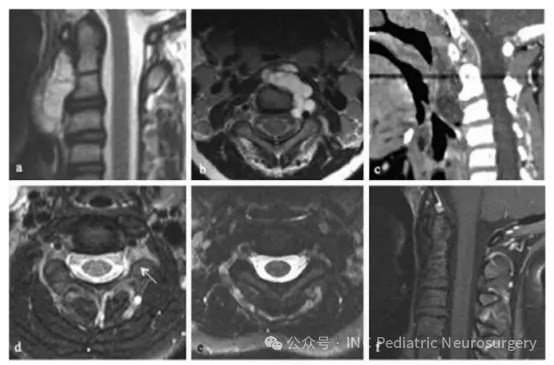

患者4

患者于2005年就诊,10岁。主诉颈部疼痛持续2年,伴反复咽喉感染及吞咽困难。检查发现C1–C3脊索瘤,并造成上气道受压(图3)。患者接受了经口活检,随后通过经口、经腭、经下颌联合入路实施肿瘤全切(gross total resection)。病理诊断为经典型脊索瘤。

术后影像显示左侧C2–C3神经孔内仍有残余病灶,经光子放疗70 Gy后控制良好。患者治疗耐受情况良好,术后10年随访无复发、无神经功能缺损,仍保持无瘤状态。

图3.患者4:C1–C3脊索瘤影像示例

(a)术前矢状位T1加权增强MRI(gadolinium);

(b)术前轴位T1加权增强MRI;

(c)术前矢状位CT;

(d)术后轴位T1加权增强MRI,可见C2–C3神经孔内小残余肿瘤(箭头);

(e)放疗后轴位T1加权增强MRI;

(f)放疗后矢状位T1加权增强MRI。